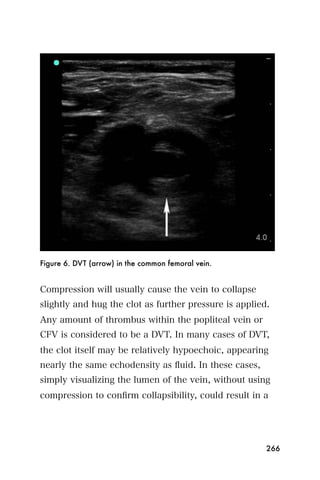

CFV	    Common Femoral Vein

DVT	    Deep Venous Thrombosis